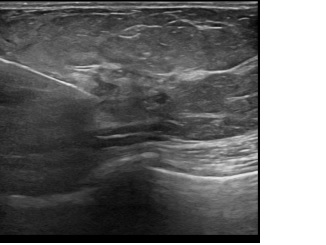

상기환자는 일주일전부터 만져지는 멍울있어 내원하신 50대 초반

여성분으로 의심스러운 좌측혹 조직검사 시행해 상피내암 진단되었습니다.